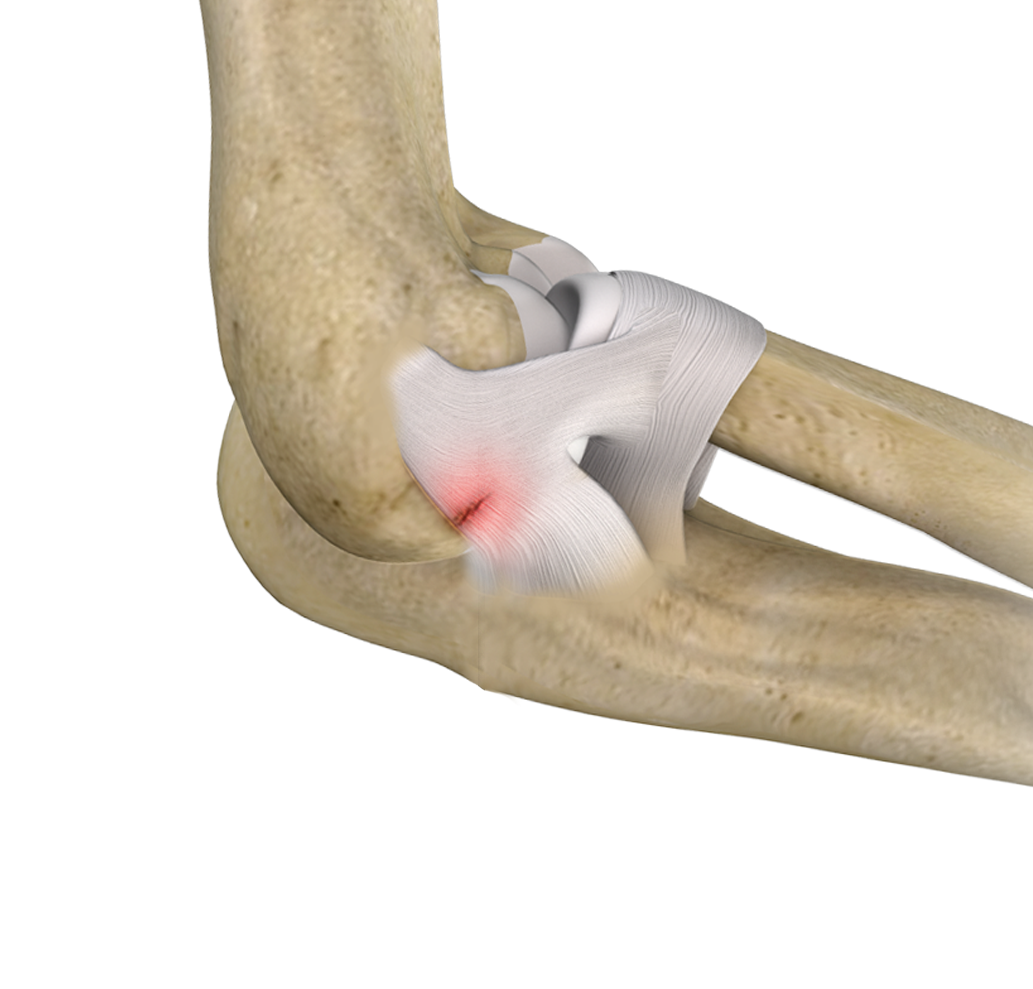

Elbow Ligament Injuries

Elbow ligament injuries are injuries to the tough elastic tissues that connect the bones of the elbow joint to each other.

Lateral Ulnar Collateral Ligament Injuries (Elbow)

A ligament is a band of elastic, tough fibrous connective tissue around a joint. It attaches bone to bone, supports and holds them together and limits the joint's movement.

Ulnar Collateral Ligament (UCL) Injury

The ulnar collateral ligament (UCL), also called the medial collateral ligament, is located on the inside of the elbow and connects the ulna bone to the humerus bone.